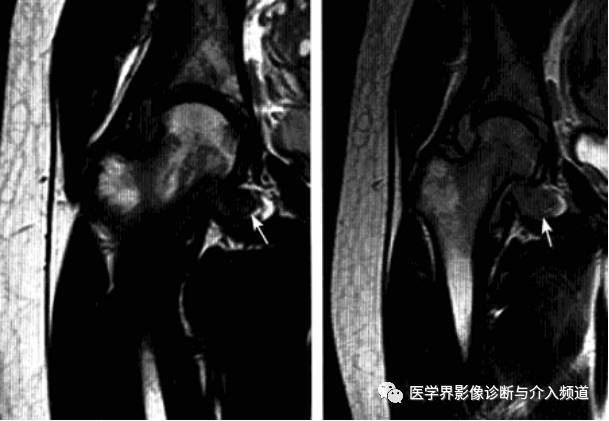

影像诊断:早期诊断缺泛特异性,晚期出现典型骨质破坏。MRI检查具较强特异性及定性诊断作用。

MRI:股骨头颈凹陷减少(α>50°),股骨颈宽度与股骨头半径比率增大,髋臼后倾。盂缘退行性改变,撕裂、囊肿,关节间隙后期出现狭窄,周围肌肉炎症。